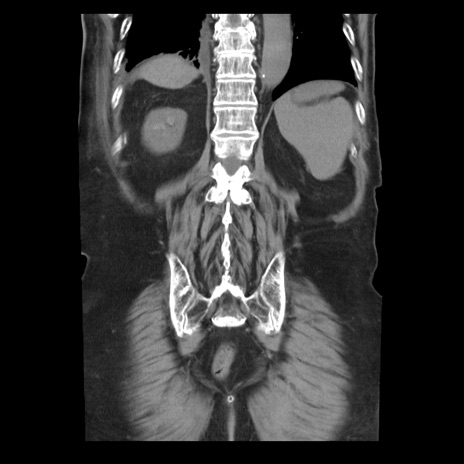

症例21(冠状断像)

【症例】70歳代男性

【主訴】腹痛

【現病歴】肝硬変・肝細胞癌にてかかりつけの方。約9時間前に食後より腹痛出現。症状が徐々に増悪し、嘔吐出現したため来院。

【既往歴】肝硬変、肝細胞癌(RFA、TACE後)

【身体所見】意識清明、表情苦悶様、BT 36℃、BP 129/78mmHg、P 88bpm、SpO2 97%(RA)、右上腹部から心窩部にかけて圧痛あり、反跳痛なし、筋性防御あり。

【データ】WBC 5800、CRP 0.16